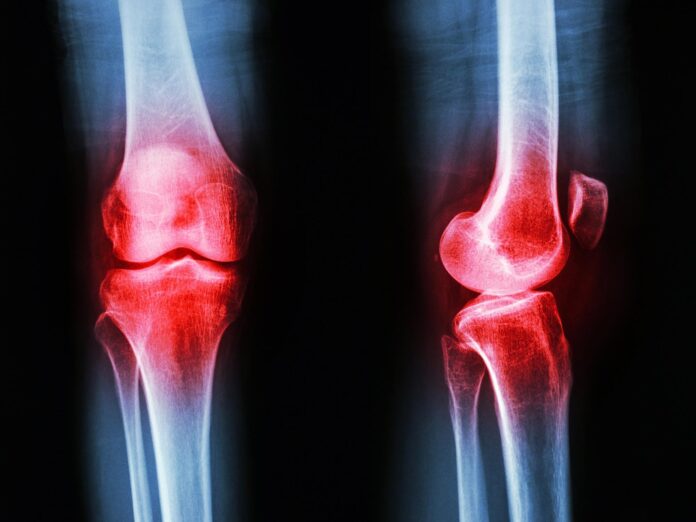

Artritis is een brede term die verschillende aandoeningen omvat, van degeneratieve artrose tot auto-immuunziekten zoals reumatoïde artritis. Hoewel deze aandoeningen qua oorsprong verschillen, delen ze allemaal een gemeenschappelijke vijand: chronische ontstekingen die leiden tot pijn, stijfheid en verlies van mobiliteit.